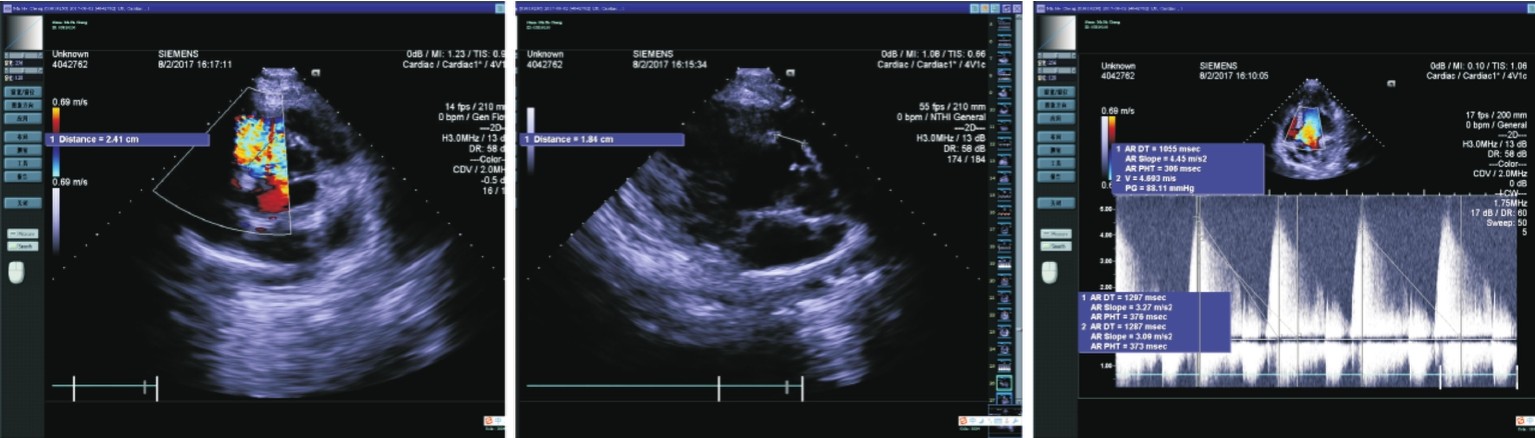

d)超声心动图(图10. 1):先天性心脏病,室间隔缺损(膜部),左心增大,升主动脉瘤样扩张,左室收缩功能稍减弱(LVEF 55%),主动脉瓣关闭不全(中重度),左室舒张功能减退,二尖瓣、三尖瓣轻度反流。

图10. 1 心超

提示:左心长轴切面见室间隔回声中断,约1. 84cm,心底短轴切面见室间隔回声中断于10~11点,约2. 41cm。心尖五腔、心尖四腔均可见收缩期五彩血流束从左室经室间隔回声中断处至右室,CWD测得分流峰值V max =4. 6m/s。PWD测收缩期经肺动脉瓣峰值流速0. 94m/s。PWD测收缩期经主动脉瓣峰值流速1. 8m/s。心尖五腔切面见一股红色五彩血流舒张期从主动脉经主动脉瓣至左室流出道,主动脉瓣左室流出道侧可探及湍流频谱,流速峰值V max =4. 7m/s,DT为1297ms。